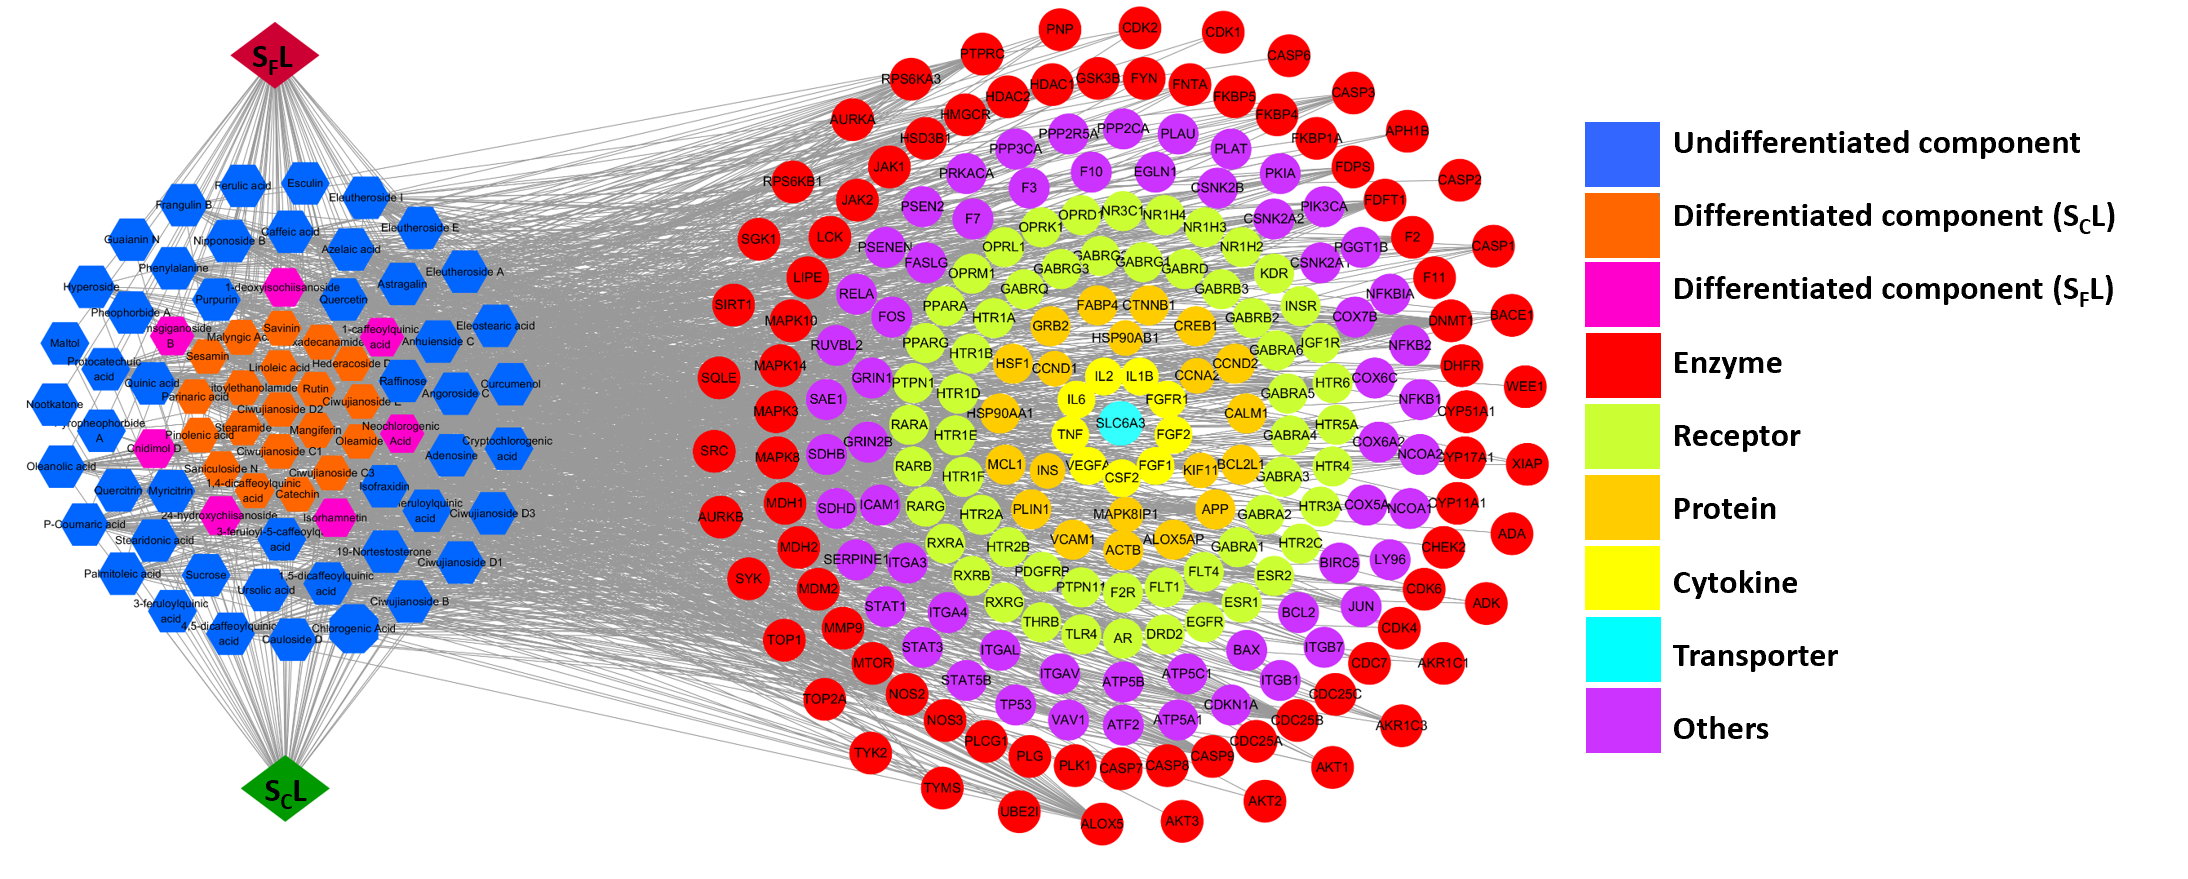

此外,研究人员通过网络药理学构建了“SCL与SFL特征成分-核心靶点-失眠”互作网络(图4),进一步揭示了非特异性和特异性化合物群是两种叶片功效相似性与差异性的物质基础。

图4“SCL与SFL特征成分-核心靶点-失眠”互作网络